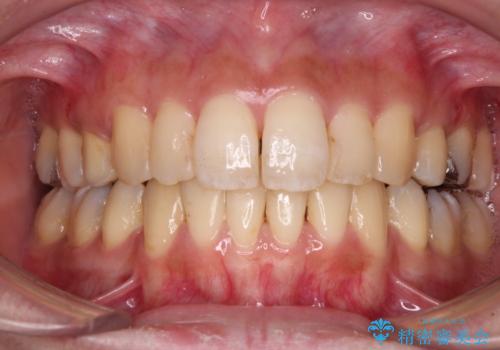

後戻りで突出した前歯をインビザラインで解消

- 抜歯矯正の後戻りで前歯が突出してきていることを気にして来院された患者様です。

口元の突出感を改善するにあたり、抜歯矯正は行うことができないため、奥歯の後方移動とIPR(歯と歯の間を削る)により達成することとしました。

再度後戻りしたときに対応しやすいよう、インビザラインにて矯正治療を行うこととしました。